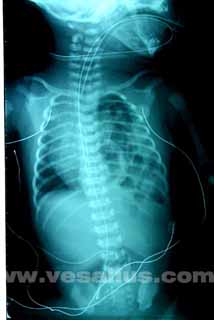

| The image on the left is a chest x-ray of an infant with CDH. The image on the right is the x-ray with a picture over it depicting the CDH. | |